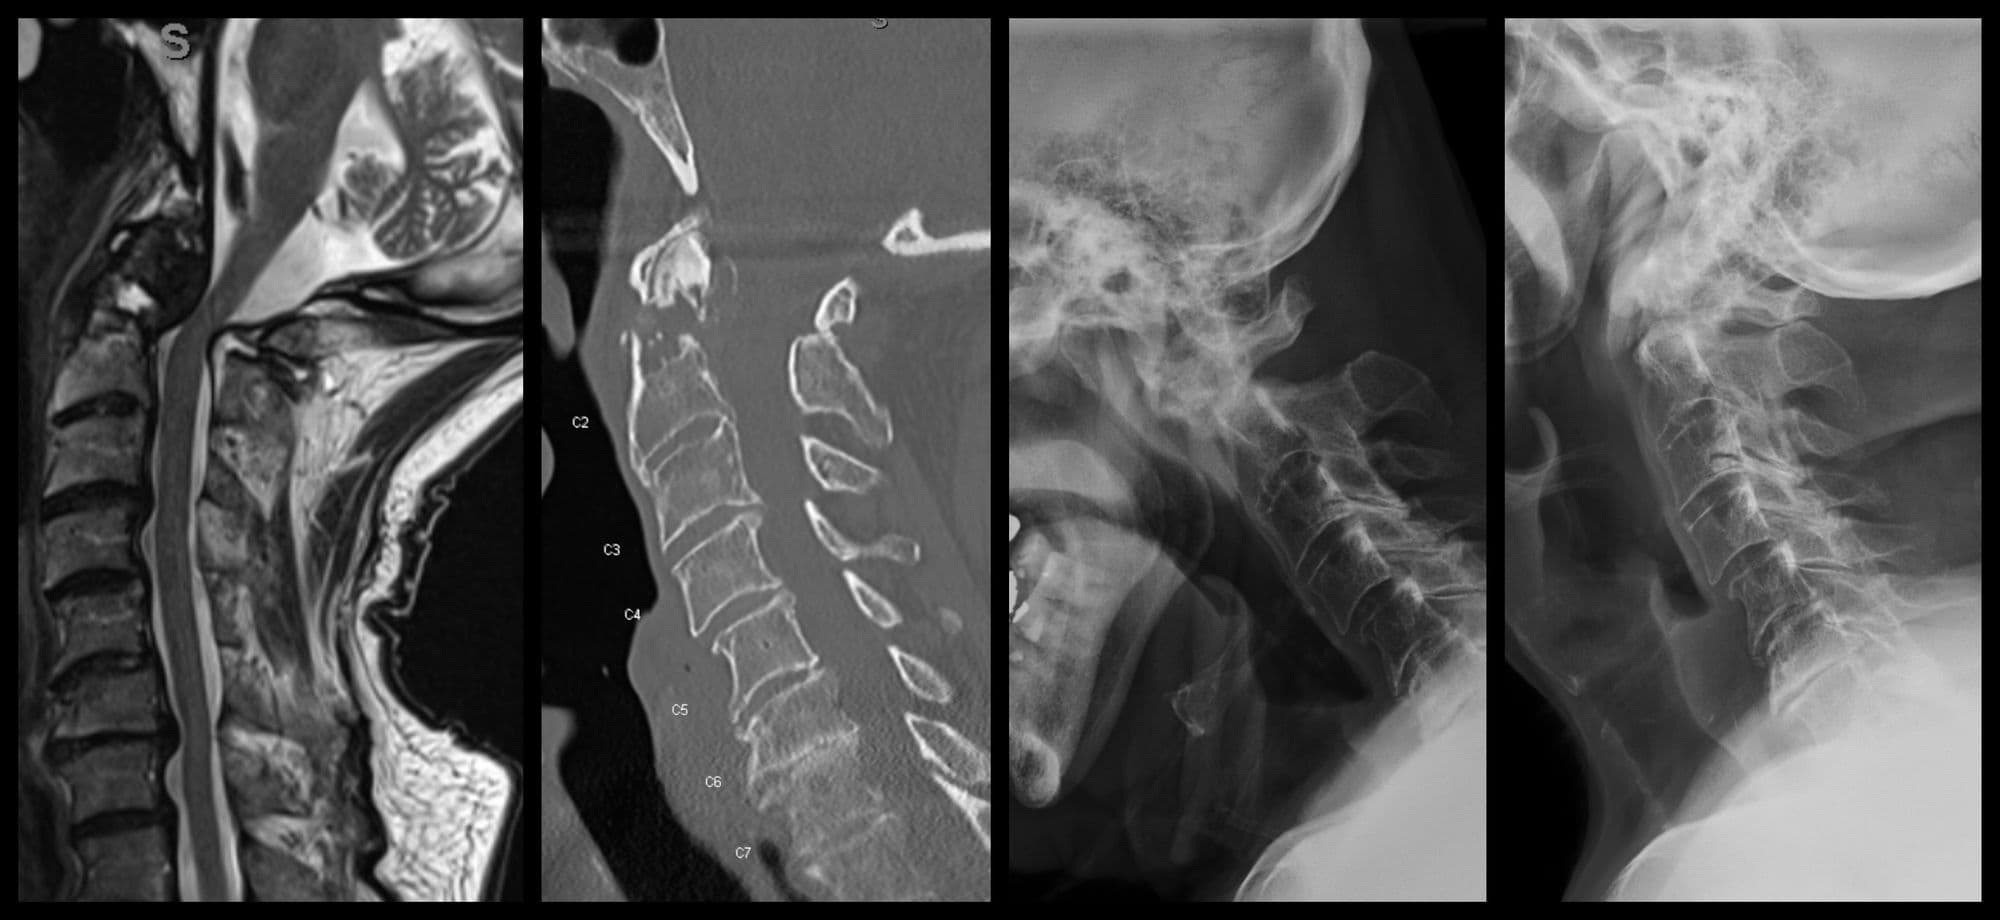

C1-2 Fusion

Darrel Brodke